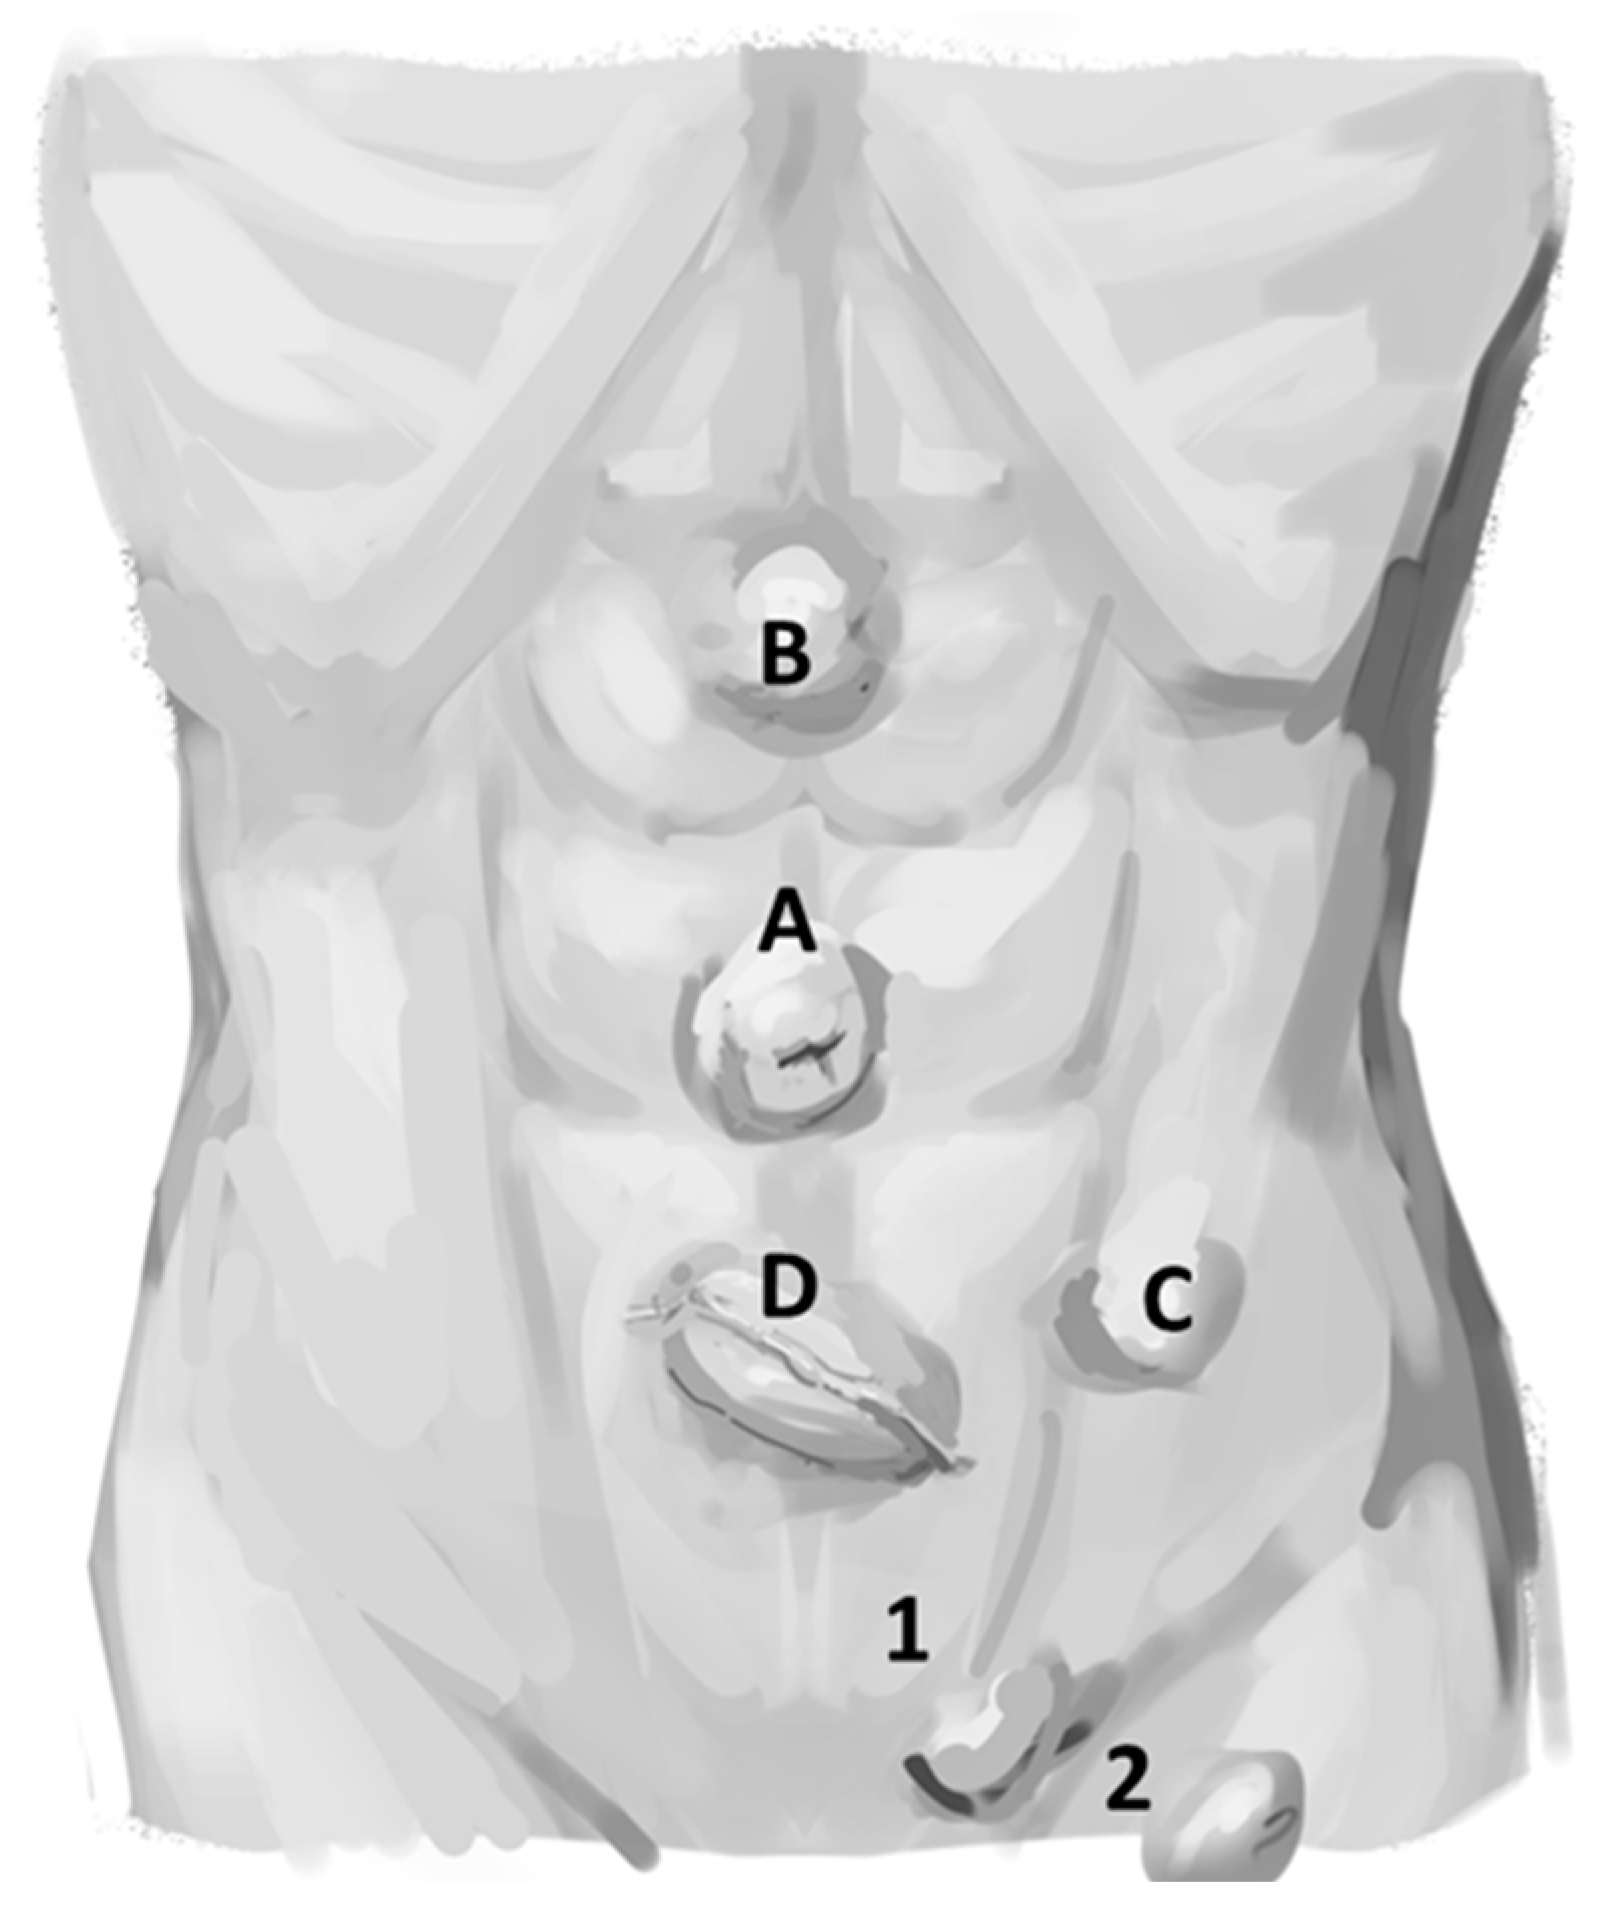

While there is a wide range of ways to define an umbilical hernia (UH), the most logical version is the one presented by the guidelines for the treatment of umbilical and epigastric hernias from the European and Americas Hernia Societies (EHS/AHS). The EHS/AHS define an UH as a primary ventral hernia with the center of the defect located in the midline in the center of the umbilical ring. This is to be contrasted with a primary epigastric hernia, defined as a ventral hernia in the midline above the umbilicus and below the xyphoid process (Figure 2) [2]. This definition should be universally adopted for consistency and management of patients with an umbilical hernia compared to epigastric hernias. An incisional hernia might be located anywhere including the midline and the umbilical ring, but this occurs after operative interventions (e.g., placement of a trocar during a laparoscopic cholecystectomy). These distinctions are important as the authors maintain that the management and outcomes of primary epigastric and incisional hernias are different from UH. This manuscript addresses the management of UH exclusively.

Figure 2. Location of umbilical hernias and epigastric hernias. A = epigastric hernia, B = Umbilical hernia. An incisional hernia can occur anywhere after an operation. 1 = Xyphoid process, 2 = linea alba. (Figure created by C. Phung).